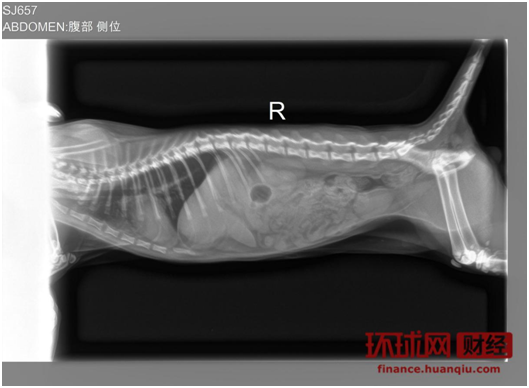

在北京自主创业的白白(化名)养了两只猫,其中一只猫不知为什么突然呕吐,白白带去附近的全心全意连锁动物医院,在医院的建议下给猫照X光,做抽血检查等,前后花费一千多元,但至今未查出任何病因。

铲屎官白白养的猫在宠物医院拍的X光。 图片来源:白白供图